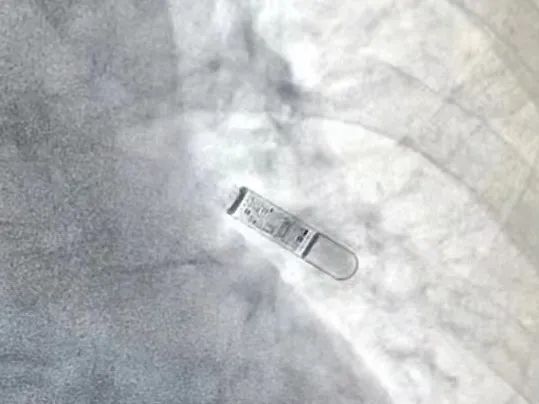

图片

植入式心电监测仪及植入后影像

于是陈样新教授与医院党委书记、心血管内科王景峰教授商量后,决定给刘伯安装植入式心电监测仪,以捕捉或鉴别刘伯晕厥是否由间歇的心律失常事件导致。出院前一天,刘伯在病房床边植入了心电监测仪。

出院后一个月,刘伯回到医院复诊,陈样新教授除了询问病史和查体以外,同时程控调取了心电监测仪里面存储的数据记录。果不其然,发现刘伯在国庆节期间的某天凌晨2点多,发生一次持续长达46秒的室性心动过速,这是一种严重威胁生命的恶性心律失常。由于持续性室性心动过速诊断明确,陈样新教授将刘伯收治入院。

“Framingham研究表明即使经过常规的无创和有创检查后仍有近40%的晕厥患者无法明确病因,其中以心源性晕厥的概率最大。”陈样新教授说道,心源性晕厥的危险性最高、预后最差,而植入式心电监测仪在明确心源性晕厥的诊断上发挥关键作用。植入式心电监测仪能连续检测心电活动近3年,并能对快速性心律失常和缓慢性心律失常进行自动记录,目前已被世界各国指南和专家共识作为不明原因晕厥和隐源性卒中(不明原因的卒中)的一线推荐。刘伯也正是因为植入式心电监测仪才明确了室性心动过速的诊断,得到了及时的治疗,有效地降低了晕厥和心脏性猝死的发生机会。

据介绍,该院王景峰教授团队早在约10余年前就开始在华南地区率先开展植入术心电监测仪(此前也叫植入式心电循环记录仪)的植入,在晕厥的诊断和鉴别诊断上,为无数患者明确了病因并给予了及时有效的治疗。而且目前袖珍的新一代植入式心电监测仪可以使用大约3年,可以兼容3.0T磁共振,还能在床边植入,极为方便,特别适合那些偶发晕厥或隐源性卒中难以捕捉证据的患者。作为中华医学会心电生理和起搏分会候任主任委员,王景峰教授带领团队在心律失常、心力衰竭等领域走在国内前列。